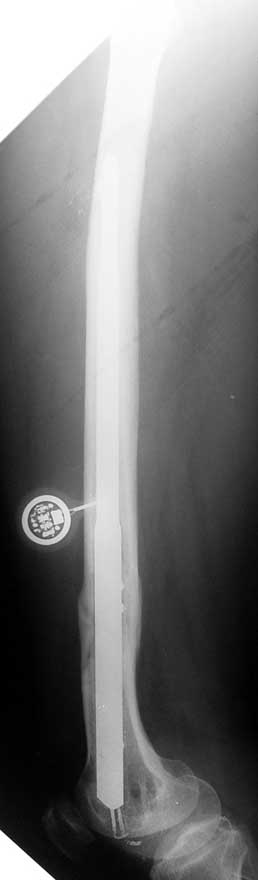

Vaka 1